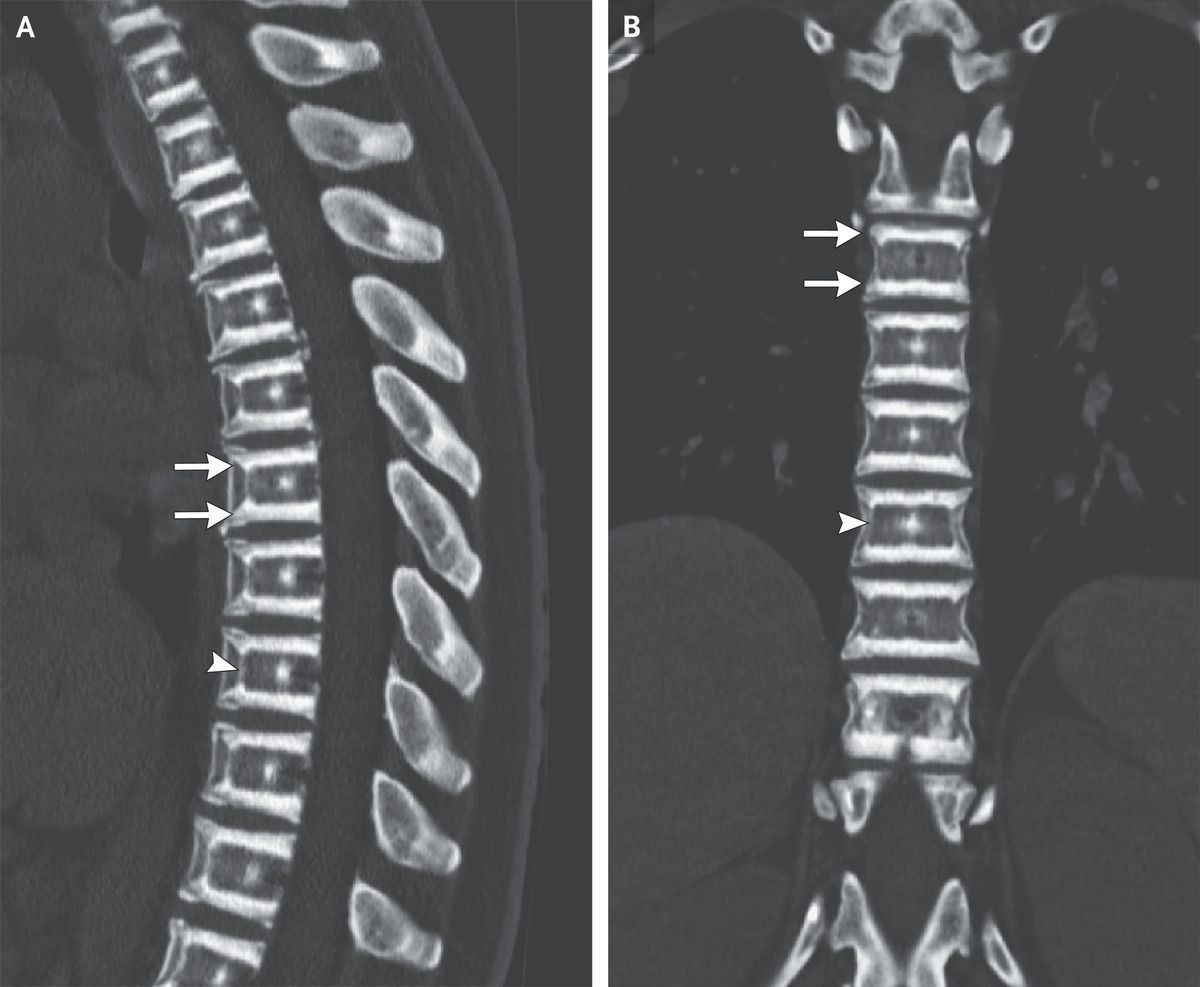

A 38-year-old woman whose father and paternal aunts had osteopetrosis presented to a primary care clinic with a 2-month history of progressive back pain. The physical examination was unremarkable. Computed tomography of the thoracic spine (Panels A and B) showed sharply demarcated sclerotic bands on the superior and inferior end plates of all vertebral bodies (arrows) — a finding known as “sandwich vertebrae.” In addition, the presence of sclerotic lines inside the vertebral bodies that were parallel to the anterior and lateral aspects of the vertebral bodies (arrowheads) created a “bone within bone” appearance. No fractures were present. Subsequent genetic testing identified a mutation in the gene CLCN7, and a diagnosis of autosomal dominant osteopetrosis, or Albers-Schönberg’s disease, was made. Osteoclasts in patients with this condition are unable to resorb bone, which causes bone density to increase, primarily in the spine, the pelvis, and the base of the skull. The radiographic findings of sandwich vertebrae and bone within bone strongly suggest the diagnosis and should prompt genetic testing. The patient’s back pain abated with supportive care. During follow-up over a period of 4 years, no compressive neuropathy or fractures developed.